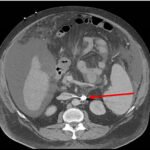

Endovascular coil embolization continues to become a more frequent modality of addressing hemorrhage and bleeding in patients. Migration refers to the coil unraveling or moving from the original embolization site. Migration of a coil is a known complication which can lead to serious consequences based on where the coil migrates. Despite increasing efforts to improve safety and technique, the risk of migration remains. We present a case of an embolization coil that migrated to the right ventricle, which was incidentally found roughly 2 months after undergoing an interventional radiology procedure for gastric variceal bleeding. The patient presented to the emergency department with dyspnea and abdominal pain. Unique images were obtained during his visit and in subsequent follow-up. As use of vascular embolization coils continues to become more commonplace, understanding the risks and complications of these procedures remains an important aspect of providing care for patients once they have left the interventional radiology suite. Coil migration should be a differential to consider in patients who present to the emergency department with signs or symptoms of arrhythmia or pulmonary embolism who have undergone a coil embolization procedure.